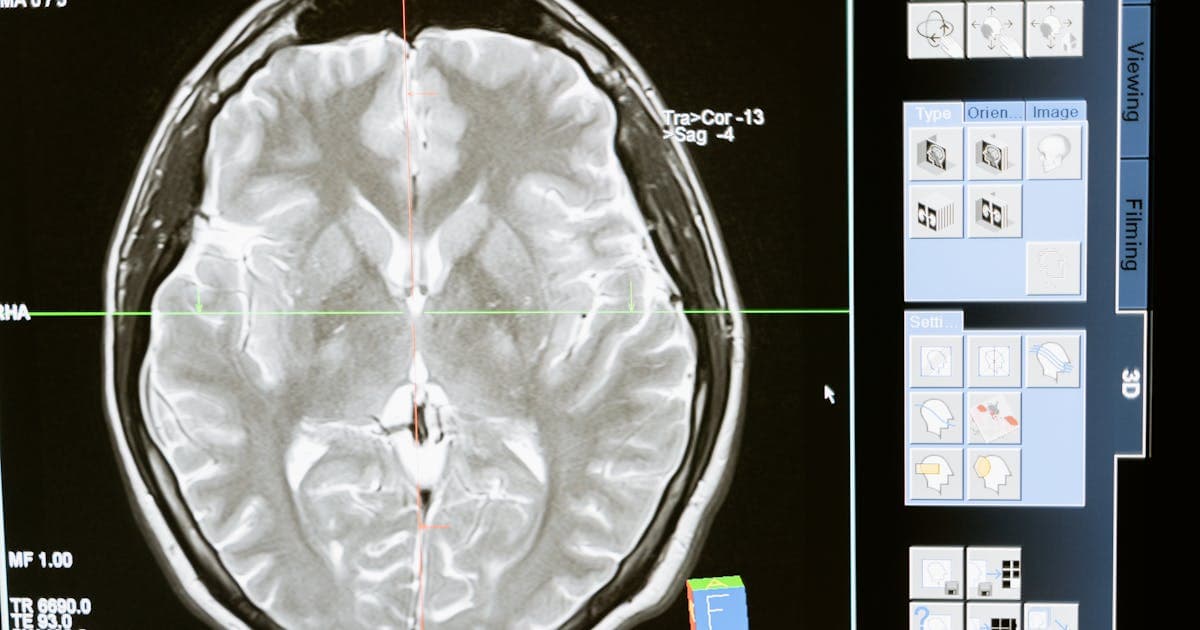

A Japanese medical device company approached BCT Global to develop an AI-powered assistant that could pre-screen chest X-rays for anomalies, helping radiologists prioritize urgent cases.

Radiologists reviewing 150+ scans daily with rising burnout. AI system needed >90% sensitivity for clinical usefulness.

• Model Development & Training (Months 3-6): Trained anomaly detection model using PyTorch; achieved 94% sensitivity, 91% specificity.